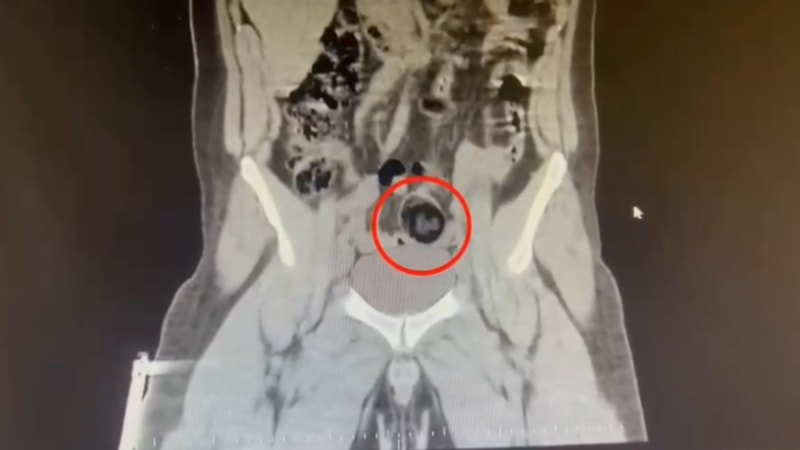

Şüpheli hareketler sergileyen kuryenin, götürüldüğü hastanede yapılan iç beden muayenesinde makatında cisim olduğu anlaşıldı.

Kuryenin makatındaki 105,98 gram metamfetamin, gerçekleştirilen cerrahi müdahaleyle çıkarıldı.